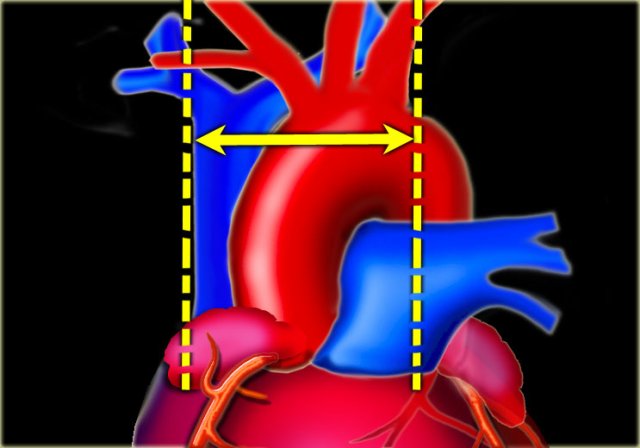

The cardiothoracic ratio (CTR) is the ratio of the transverse diameter of the heart to the internal diameter of the chest at its widest point just above the dome of the diaphragm as measured on a PA chest film.

An increased cardiac silhouette is almost always the result of cardiomegaly, but occasionally it is due to pericardial effusion or even fat deposition.

The heart size is considered too large when the CTR is > 50% on a PA chest x-ray.

A CTR of > 50% has a sensitivity of 50% for CHF and a specificity of 75-80%.

An increase in left ventricular volume of at least 66% is necessary before it is noticeable on a chest x-ray.